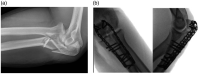

Background: Elbow fracture dislocations are complex injuries that can provide a challenge for experienced surgeons. Current classifications fail to provide a comprehensive system that encompasses all of the elements and patterns seen in elbow fracture dislocations.

Methods: The commonly used elbow fracture dislocation classifications are reviewed and the three-column concept of elbow fracture dislocation is described. This concept is applied to the currently recognised injury patterns and the literature on management algorithms.

Results: Current elbow fracture dislocation classification systems only describe one element of the injury, or only include one pattern of elbow fracture dislocation. A new comprehensive classification system based on the three-column concept of elbow fracture dislocation is presented with a suggested algorithm for managing each injury pattern.

Discussion: The three-column concept may improve understanding of injury patterns and treatment and leads to a comprehensive classification of elbow fracture dislocations with algorithms to guide treatment.